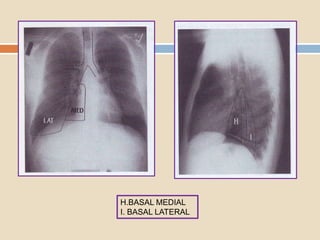

Dos segmentos basales están localizados

en posición anterior: el medial y anterior ;

dos segmentos basales hacia atrás : el

lateral y posterior.

Los dos segmentos basales

que están en contacto con la

cisura mayor son el medial y

el anterior.

Los dos que están en la

pared torácica posterior son

el posterior y medial.

H.BASAL MEDIAL

I. BASAL LATERAL